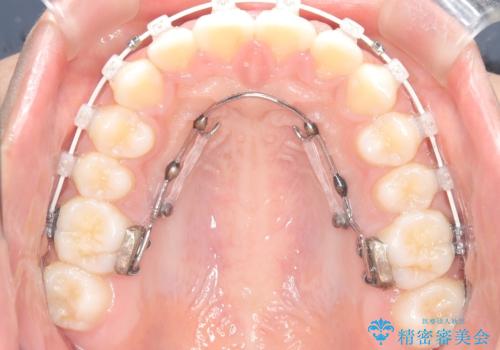

- 患者様は前歯の突出を主訴に来院されました。診査の結果、上顎の前歯が前方に傾斜しており、口元がやや突出して見える状態でした。一般的にこのようなケースでは抜歯矯正が選択肢となりますが、**患者様が抜歯を希望されなかったため、非抜歯での遠心移動(奥へ動かす治療)を計画しました。そのため、リンガルアーチ(歯の裏側に装着する装置)とTAD(歯科矯正用アンカースクリュー)**を併用し、上顎の歯を後方へ移動させながら噛み合わせを整える方法を選択しました。

まず、上顎にリンガルアーチを装着し、歯列の幅を適正に維持しながら遠心移動をサポート。さらに、**TAD(矯正用アンカースクリュー)**を利用することで、奥歯を固定源とせずに前歯だけを後方へ移動させることが可能になりました。これにより、抜歯をせずに前歯の突出を抑え、バランスの取れた口元へと改善。治療後、患者様からは「抜歯せずに理想の仕上がりになり、大満足」とのお声をいただきました。